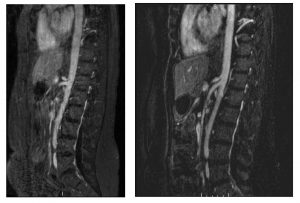

Median arcuate ligament syndrome

Patients with chronic post-prandial epigastric pain may have median arcuate ligament syndrome (MALS). The median arcuate ligament is a part of the diaphragm that surrounds the aorta. The diaphragm moves with respiration. In theory, this movement may cause tension on the celiac artery or on the nerves surrounding the celiac plexus. But there is much…